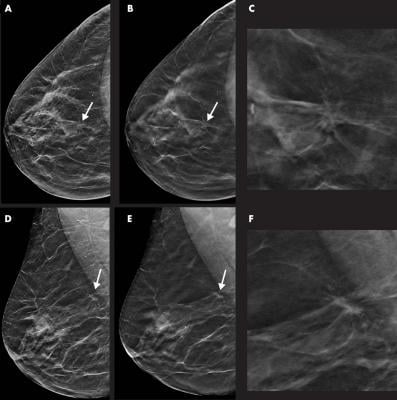

Images in a 55-year-old woman with a spiculated mass localized in the upper central quadrant (arrow in A, B, D, and E) of right breast detected with digital breast tomosynthesis (DBT) plus synthetic mammography (SM). Breast density was classified as category C with the Breast Imaging Reporting and Data System. Mass was invasive ductal carcinoma, stage I, and was estrogen and progesterone receptor positive and human epidermal growth factor receptor 2 negative. A, Image from SM in craniocaudal view. B, Single-slice DBT image in craniocaudal view. C, Magnification of the lesion depicted in B. D, Image from SM in mediolateral oblique view. E, Single-slice DBT image in mediolateral oblique view. F, Magnification of the lesion depicted in E. Images courtesy of Radiological Society of North America